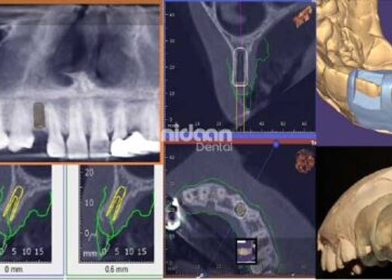

Virtual implant planning & Guide Designing